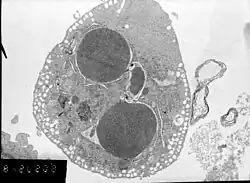

Физика медицинской визуализации также известна как физика диагностической и интервенционной радиологии. Клинические (как «штатные», так и «консультирующие») физики[14] обычно занимаются областями тестирования, оптимизации и обеспечения качества таких областей физики диагностической радиологии, как рентгенография, рентгеноскопия, маммография, ангиография и компьютерная томография. , а также методы неионизирующего излучения, такие как УЗИ и МРТ. Они также могут заниматься вопросами радиационной защиты, такими как дозиметрия (для персонала и пациентов). Кроме того, многие физики-визуалисты часто также связаны с системами ядерной медицины, включая однофотонную эмиссионную компьютерную томографию (ОФЭКТ) и позитронно-эмиссионную томографию (ПЭТ). Иногда физики-визуалисты могут заниматься клиническими областями, но в исследовательских и учебных целях[15], например, для количественной оценки внутрисосудистого ультразвука как возможного метода визуализации конкретного сосудистого объекта. В некоторых случаях для научных исследований и диагностики структур и функций на микро- нано-уровне целесообразно использование электронной микроскопии[16][17].